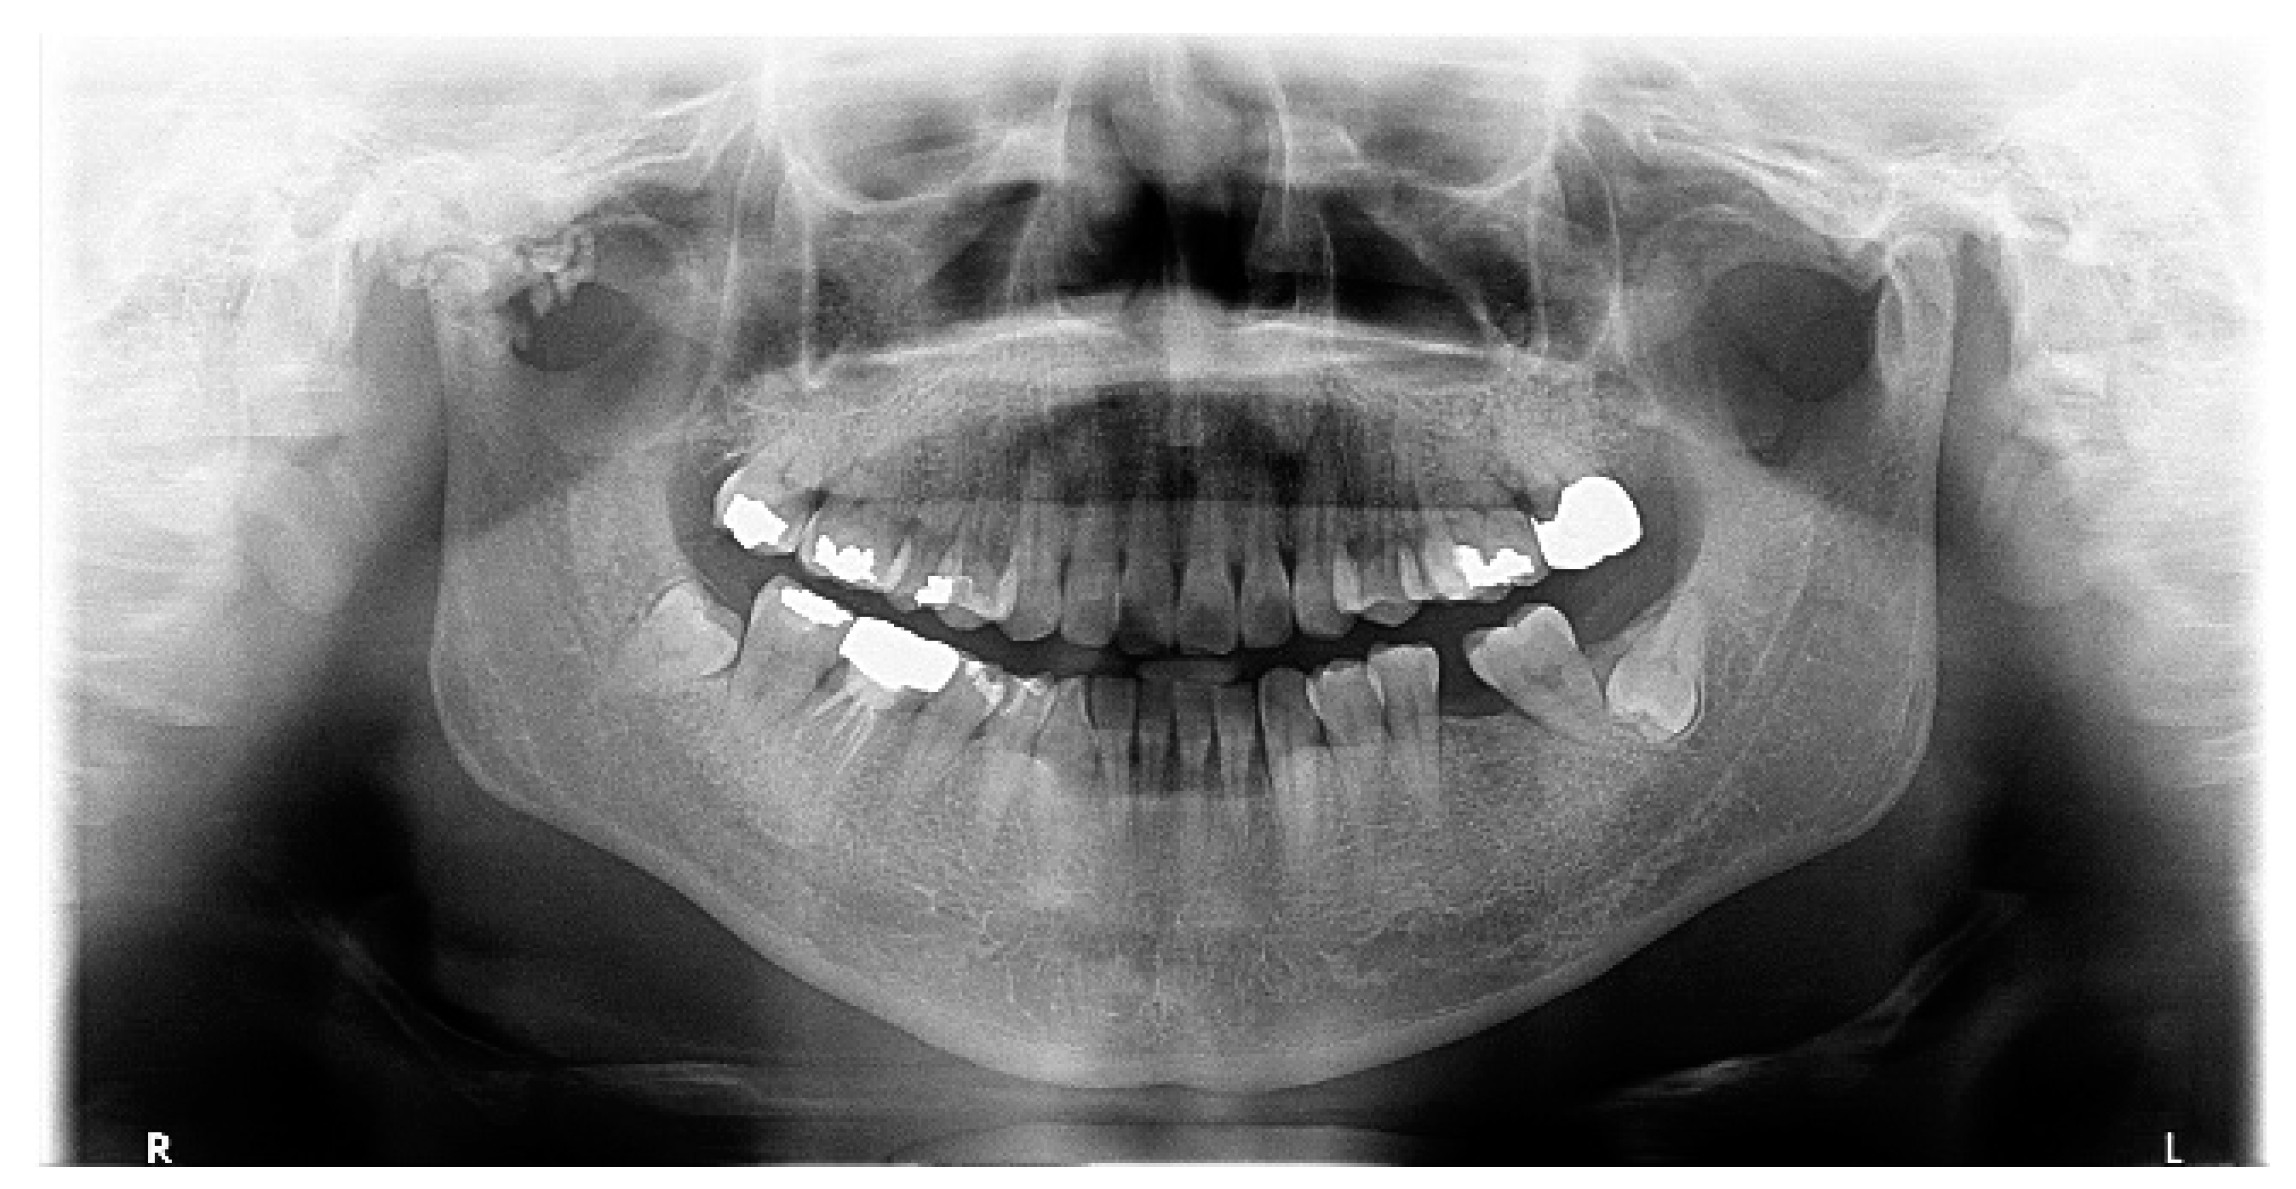

Extensive Synovial Chondromatosis of the Temporomandibular Joint Extending to the Cranial Base